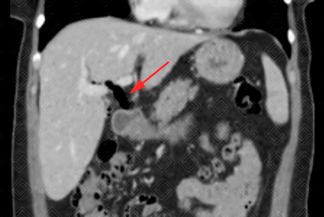

Texto alternativo para a imagem Figuras 1, 2, 3 e 4. Créditos: Dra. Elazir Mota - Rio de Janeiro/RJ.

Descrição das figuras 1, 2, 3 e 4: Tomografia computadorizada do abdome. Estudo pós-contraste (fase portal), cortes axiais e coronais evidenciando a presença de gás (setas vermelhas) no interior do colédoco e via biliar intra-hepática esquerda. Após colher nova história com a paciente, havia relato de procedimento recente (colangiopancreatografia retrógrada endoscópica [CPRE]).

Aerobilia: Também chamada de pneumobilia. Trata-se da presença de gás no interior da árvore biliar. As principais etiologias são abordagem recente das vias biliares (CPRE, colangiografia intra-operatória), incompetência do esfíncter de Oddi (congênita, uso de atropina, esfincterotomia e pancreatite crônica), fístula bilioentérica, processos infecciosos (colangite, colecistite enfisematosa, abscesso hepático e ruptura de cisto hidático).